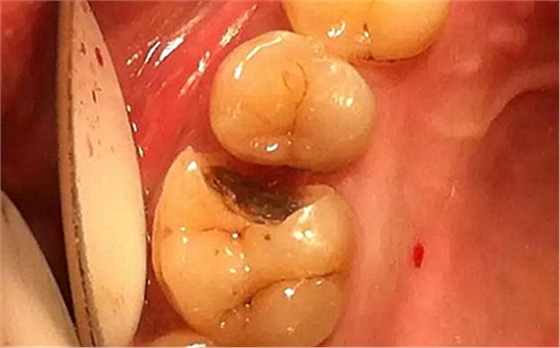

下面為一例纖維樁全冠修復(fù)后,纖維樁斷裂的病例,同樣實(shí)行了冠延長手術(shù)。

患者女性,55歲,3年前B3纖維樁+鑄瓷全冠修復(fù),一周前牙冠折斷,就診后,發(fā)現(xiàn)纖維樁根管口處折斷,周圍牙齦增生,建議患者行冠延長手術(shù)。首先去除斷端的纖維樁。拍片示牙根長度充足。于是開始冠延長手術(shù)。

因?yàn)槭乔把溃试摶颊邔硇迯?fù)體邊緣必須為齦下,所以3個月后再行修復(fù)。以下為手術(shù)前照片。

以下為術(shù)中照片。